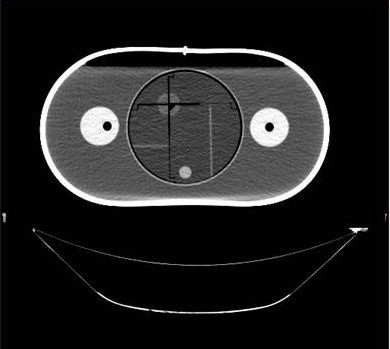

IROC Houston has developed a liver phantom. The phantom includes a liver with two targets, and 2 organs at risk. Click here for irradiation guidelines and forms for photon therapy, and click here for guidelines for proton therapy.